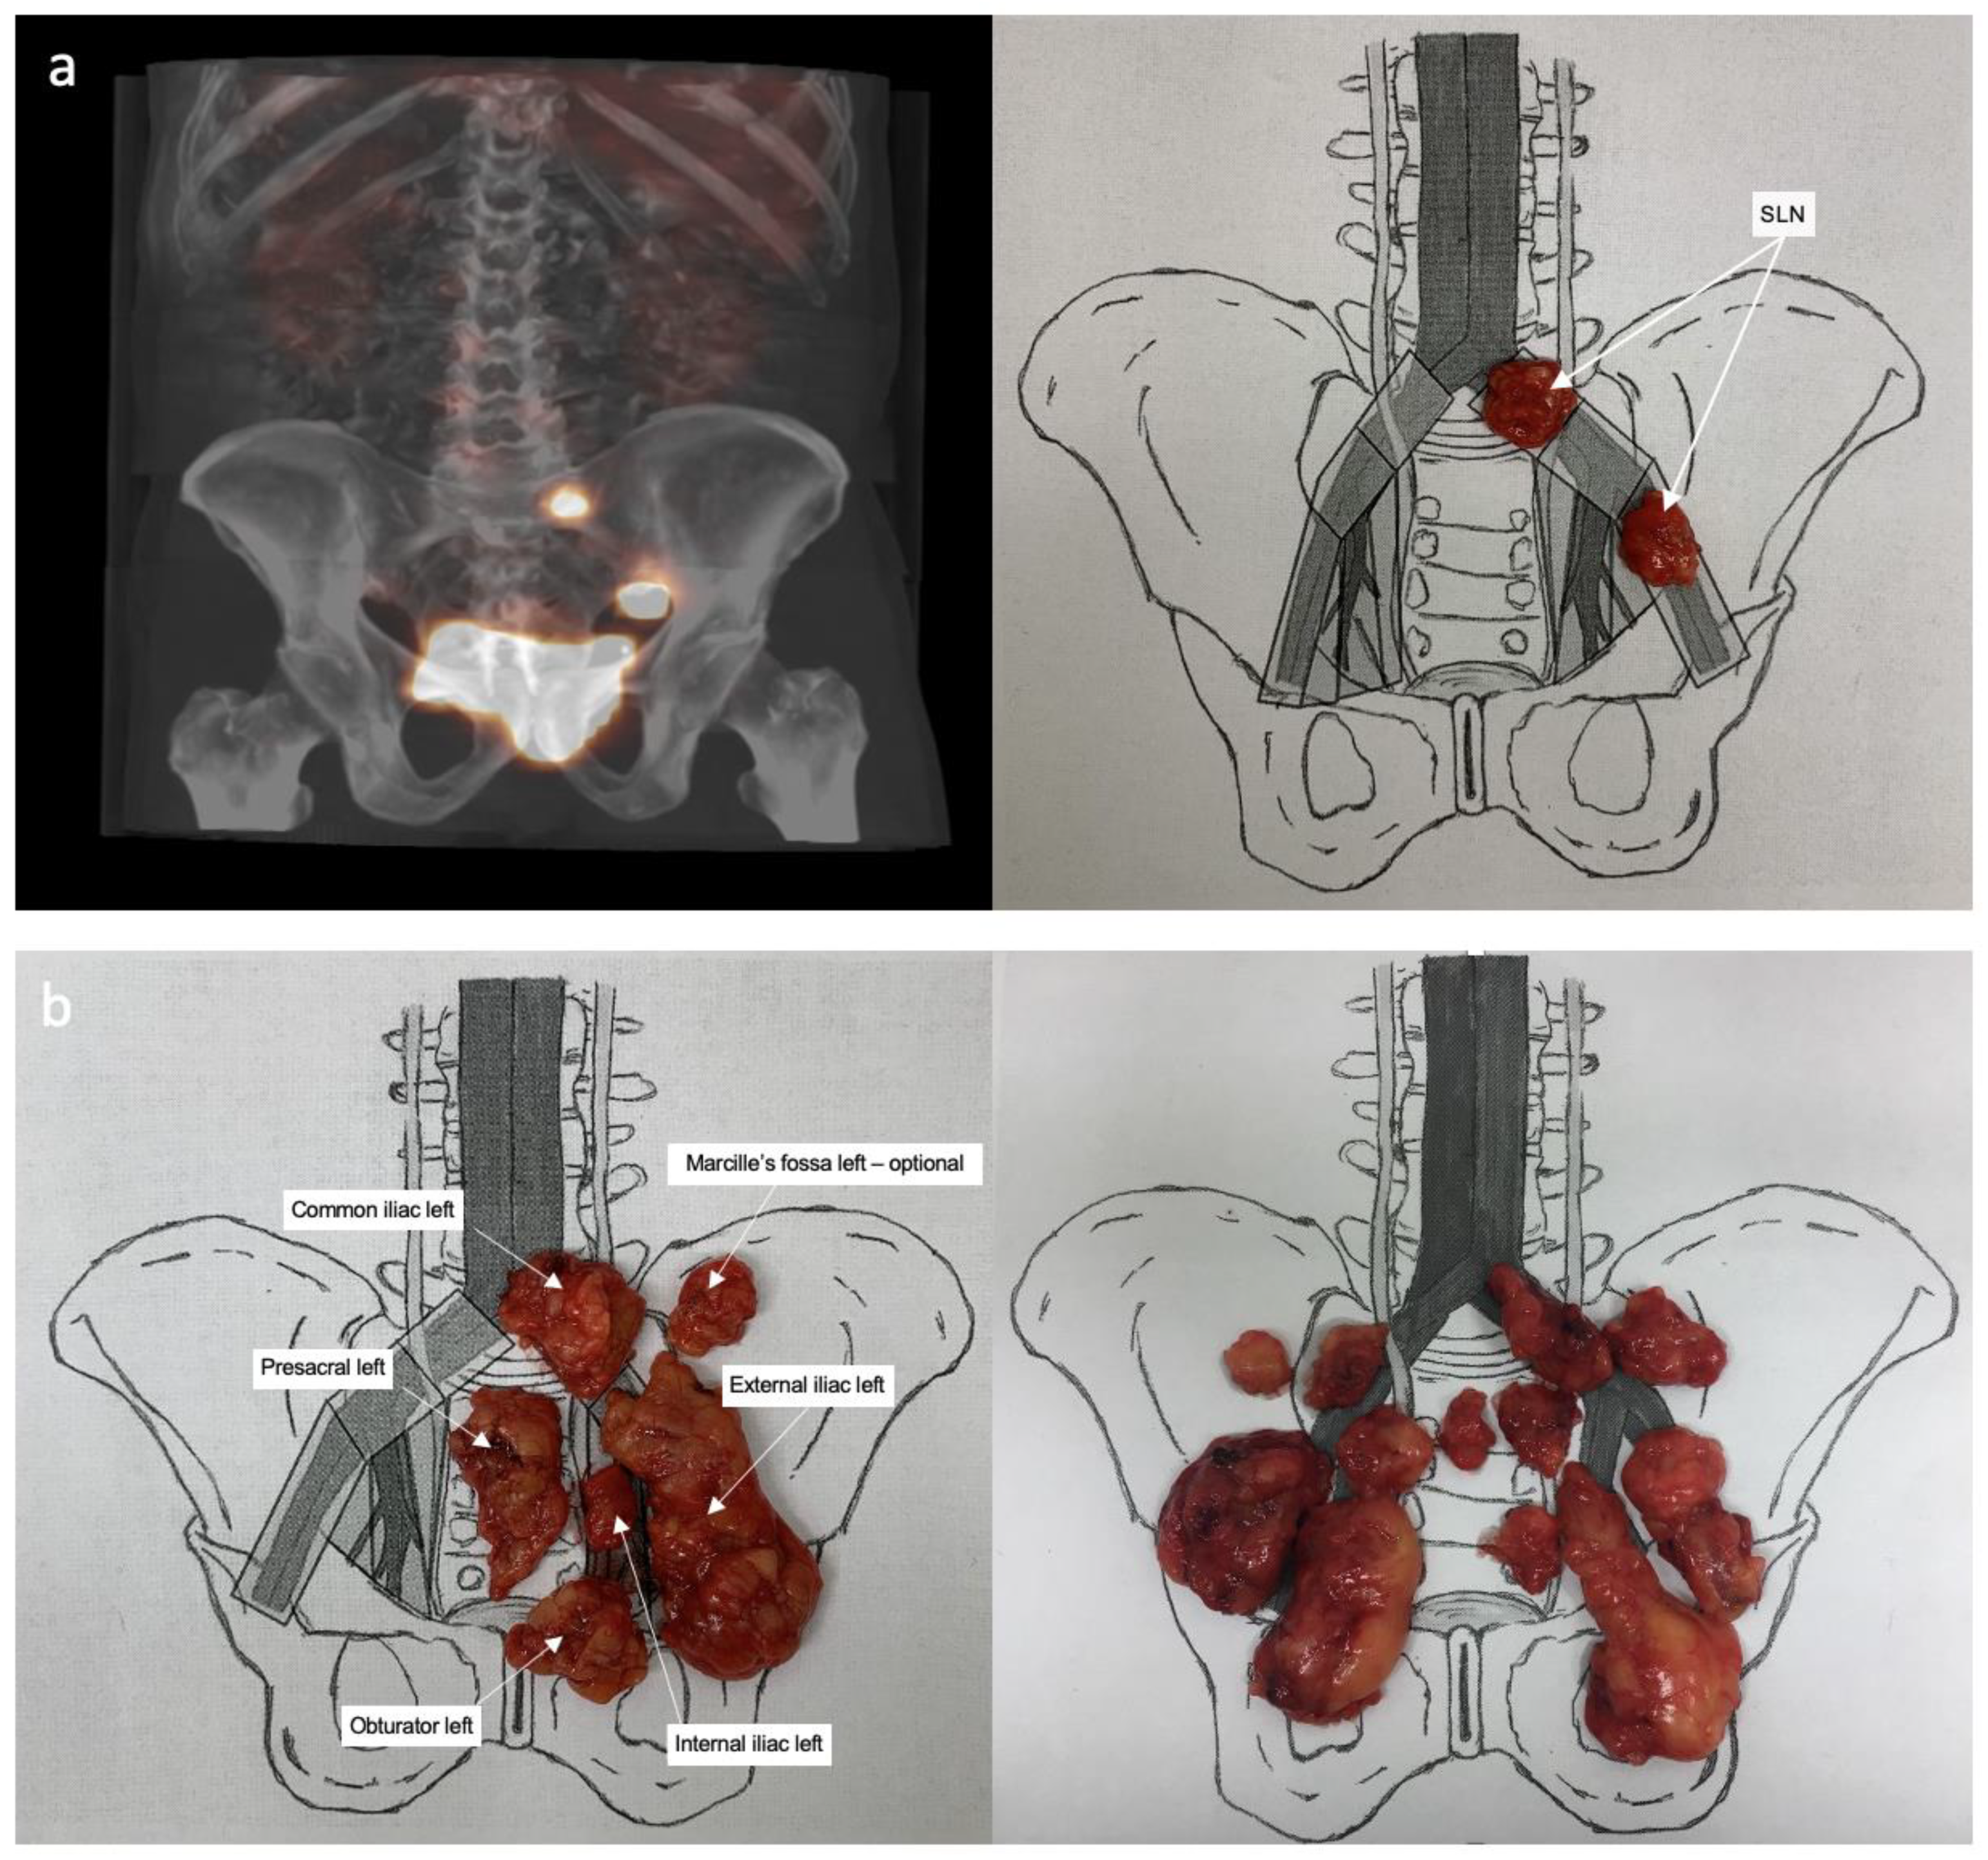

2.3. Surgical Procedure

3.2. Sentinel Lymph Node Detection

3.3. Lymph Node Characteristics